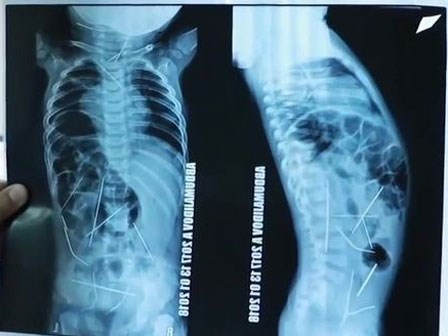

Con sốt cao, tiểu tiện khó khăn, mẹ đưa đến bệnh viện và ngã quỵ khi nhìn thấy hình chụp X-quang

Những hình ảnh kinh hoàng từ hình chụp X-quang của đứa trẻ 11 tháng tuổi khiến người mẹ và các bác sĩ không thể tin vào mắt của mình.